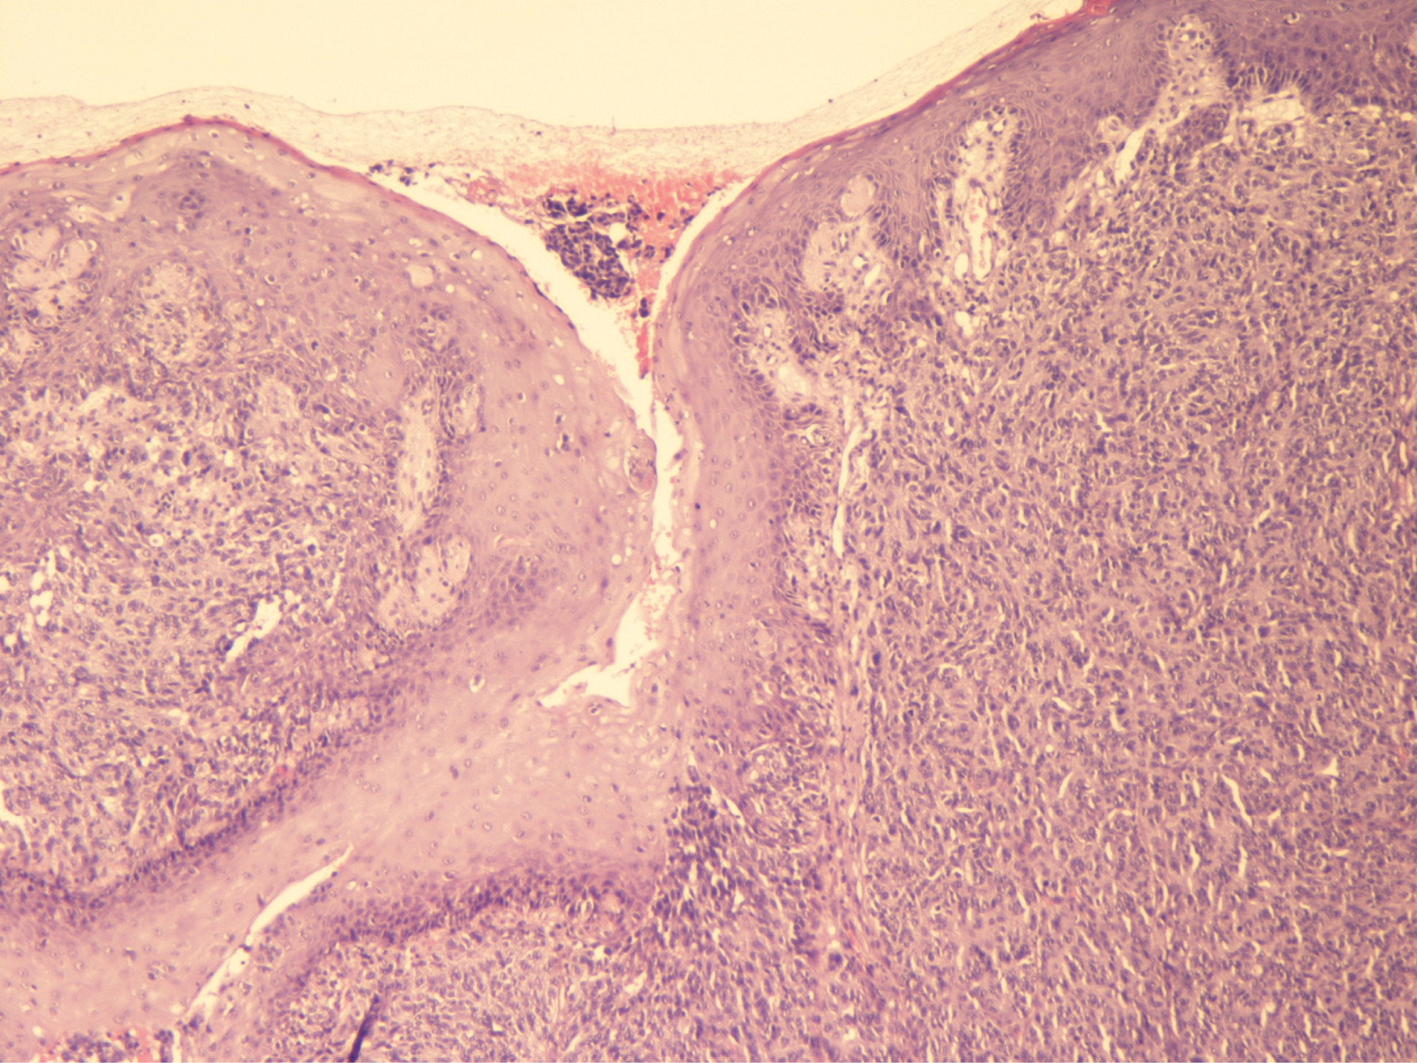

Fig 2

Figure 2 This image demonstrates hyperplasia of the epidermis, an atypical dermal melanocytic proliferation, with several ectatic vessels and a lymphocytic infiltrate. Sometimes it is difficult to distinguish between a metastasis and a primary head and neck mucosal melanoma. (Hematoxylin and Eosin, 20×). Courtesy of Dr. Angelina Pernazza.